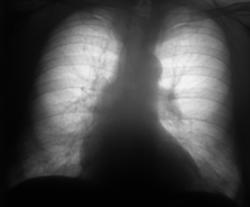

При расшифровке флюорограграмм (2007) пациент был "взят на контроль" - на уровне 4 ребра слева обнаружена крупноочаговая тень.

Провели рентгенографию в прямой стандартной проекции. С учетом "неубедительности" теневой картины "решили понаблюдать".

2008 г. Пациент "взят на контроль"

Зафиксировано увеличение тени в размерах. Произведена рентгенография в прямой стандартной проекции.

Было высказано предположение о наличии "маленького периферического рака", зафиксирована "линзеподобная тень" паракостально. Пациент направлен на консультацию в онкологический диспансер.